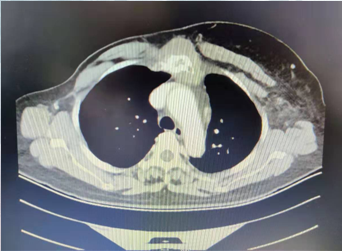

影像学检查:2018-9-11CT示:左乳术后缺如,胸骨及肋骨周围见软组织肿块影。骨窗示:胸骨及右侧部分肋骨骨质破坏。

2019-02-12CT示:胸骨及肋骨周围软组织肿块影较前缩小,但并未恢复正常,胸骨及肋骨修复性改变。

2019-08-27CT示:胸骨及肋骨周围软组织浸润不明显,胸骨及肋骨修复性改变。